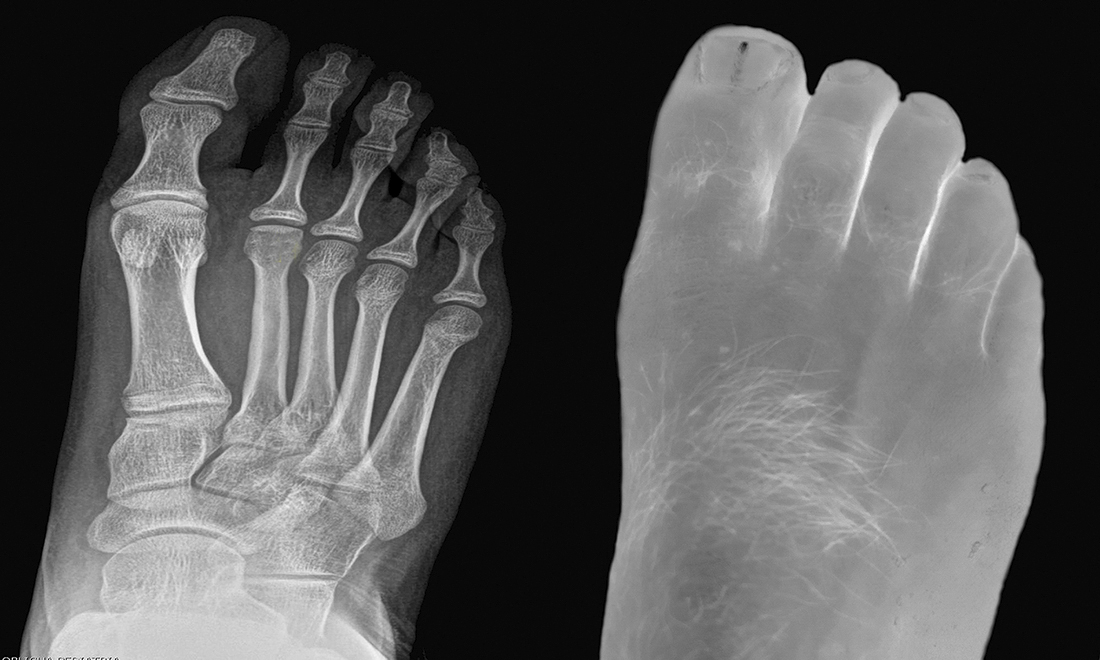

With a look devoid of fears, almost analytical, the author studies, through his own body, his three states or realities: the external (epidermis), the internal, and the inevitable future that is to come (it is said that we started to die from the moment we are born) .